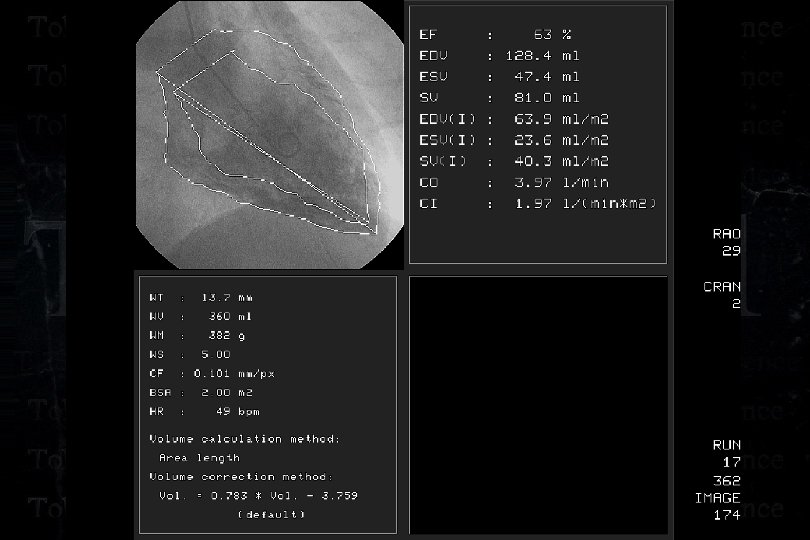

Effort AP, 54 years, male: Ostial LAD CTO

Effort AP, 54 years, male: Ostial LAD CTO

Effort AP, 54 years, male: Ostial LAD CTO

Effort AP, 54 years, male: Ostial LAD CTO

Effort AP, 54 years, male: Ostial LAD CTO

Effort AP, 54 years, male: Ostial LAD CTO

Effort AP, 54 years, male: Ostial LAD CTO Separated Conus Branch !